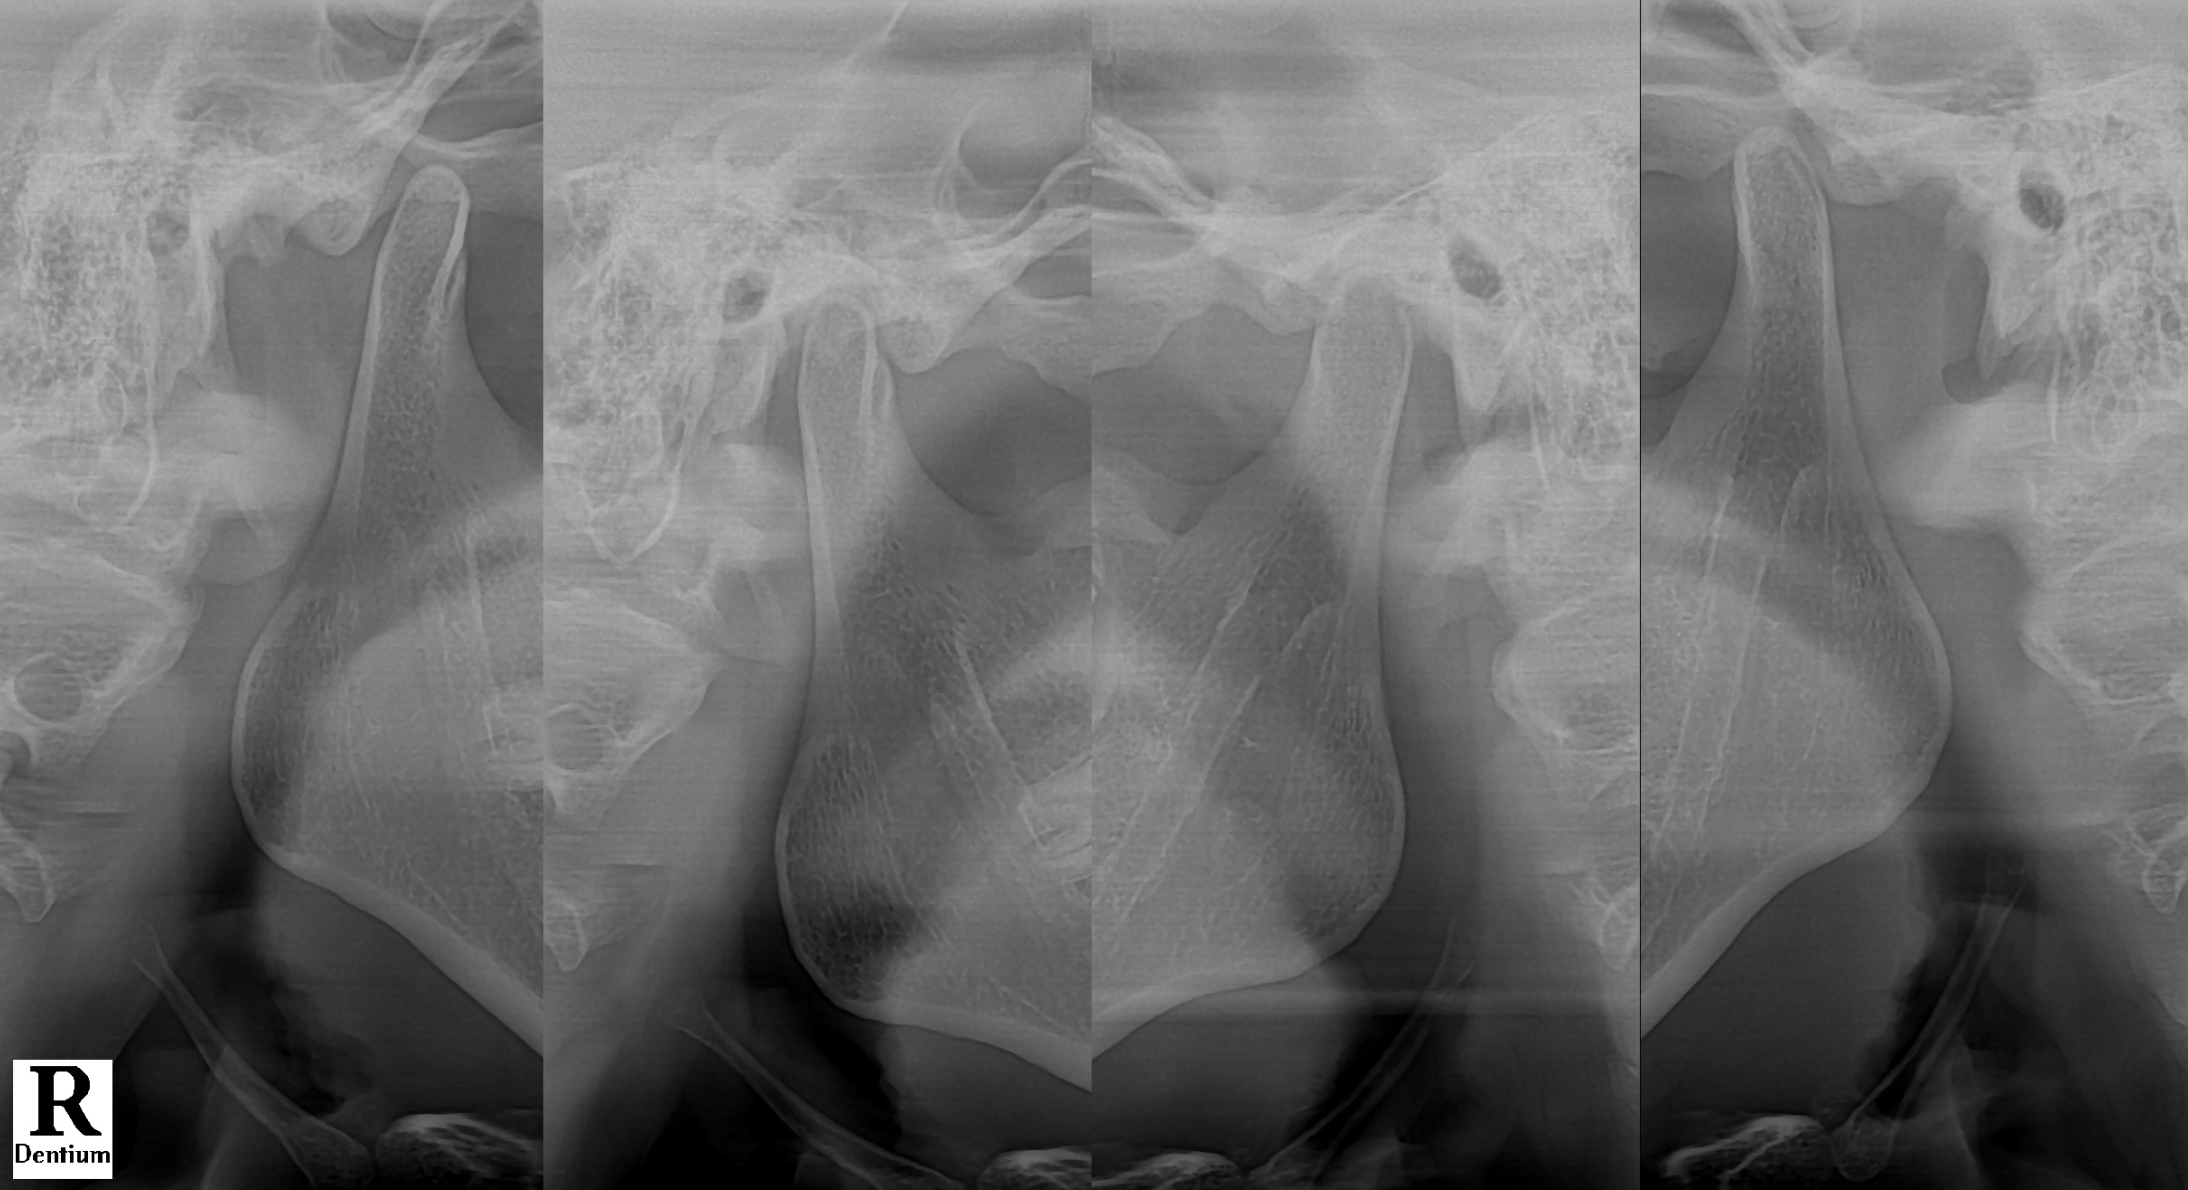

귀가 아파서 병원 갔는데, 원인은 턱관절이었습니다

#CaseNo240466